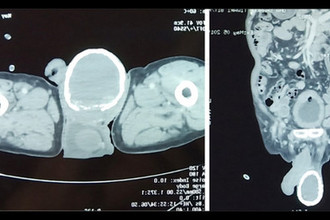

Врачи стали диагностировать у него не до конца опущенные яички . Есть ли вероятность, что они еще опустятся? Если да, то что для этого надо делать? Если нет, то что его ждет — операция? Виолетта